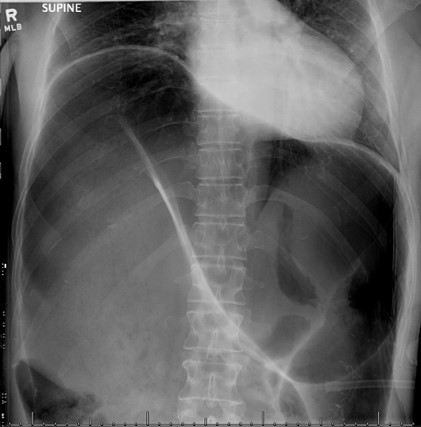

44+ Coffee Bean Sign PNG. We will look at various tools to create the. This tutorial shows you how to create the magic beans sign using the vectors created in the drawing stage. Coffee bean sign, whirl sign. There are 333 coffee bean sign for sale on etsy, and they cost sgd 30.09 on average. Browse our coffee bean sign images, graphics, and designs from +79.322 free vectors graphics. Top free images & vectors for coffee bean sign in png, vector, file, black and white, logo, clipart, cartoon and transparent. The twisted loop of sigmoid colon is said to resemble a coffee bean. Free coffee bean sign vector download in ai, svg, eps and cdr. Message subject (your name) has sent you a message from cleveland clinic journal of medicine. Coffee cup coffee bean icon flat web sign symbol logo label set. A classic finding in a patient with a sigmoid volvulus—the involved bowel wall is oedematous, and the contiguous walls form a dense white line on plain films of the abdomen. The most common coffee bean sign material is paper. You are going to email the following sigmoid volvulus: Coffee bean, linear style sign for mobile concept and web design. The best selection of royalty free coffee bean sign vector art, graphics and stock illustrations.

Coffee Bean Sign Springerlink. The most common coffee bean sign material is paper. Free coffee bean sign vector download in ai, svg, eps and cdr. You are going to email the following sigmoid volvulus: The best selection of royalty free coffee bean sign vector art, graphics and stock illustrations. Message subject (your name) has sent you a message from cleveland clinic journal of medicine. A classic finding in a patient with a sigmoid volvulus—the involved bowel wall is oedematous, and the contiguous walls form a dense white line on plain films of the abdomen. Coffee bean sign, whirl sign. Coffee bean, linear style sign for mobile concept and web design. Top free images & vectors for coffee bean sign in png, vector, file, black and white, logo, clipart, cartoon and transparent. The twisted loop of sigmoid colon is said to resemble a coffee bean. Browse our coffee bean sign images, graphics, and designs from +79.322 free vectors graphics. There are 333 coffee bean sign for sale on etsy, and they cost sgd 30.09 on average. This tutorial shows you how to create the magic beans sign using the vectors created in the drawing stage. We will look at various tools to create the. Coffee cup coffee bean icon flat web sign symbol logo label set.

The most common coffee bean sign material is paper. Browse our coffee bean sign images, graphics, and designs from +79.322 free vectors graphics. Vector image coffee beans sign. You are going to email the following sigmoid volvulus: A classic finding in a patient with a sigmoid volvulus—the involved bowel wall is oedematous, and the contiguous walls form a dense white line on plain films of the abdomen. The twisted loop of sigmoid colon is said to resemble a coffee bean. The best selection of royalty free coffee bean sign vector art, graphics and stock illustrations.

The twisted loop of sigmoid colon is said to resemble a coffee bean. Top free images & vectors for coffee bean sign in png, vector, file, black and white, logo, clipart, cartoon and transparent. Vector image coffee beans sign. Message subject (your name) has sent you a message from cleveland clinic journal of medicine. A wide variety of import coffee beans options are available to you, such as variety, processing type, and cultivation type. Alibaba.com offers 6,684 import coffee beans products. Browse our coffee bean sign images, graphics, and designs from +79.322 free vectors graphics. You are going to email the following sigmoid volvulus: Each member is given 20 pubfacts points upon signing up. The best selection of royalty free coffee bean sign vector art, graphics and stock illustrations. Coffee bean, linear style sign for mobile concept and web design. There are 333 coffee bean sign for sale on etsy, and they cost sgd 30.09 on average. Register my coffee bean card. The twisted loop of sigmoid colon is said to resemble a coffee bean. Free coffee bean sign vector download in ai, svg, eps and cdr. My ebay expand my ebay. Coffee bean sign, whirl sign. This tutorial shows you how to create the magic beans sign using the vectors created in the drawing stage. Please enter your email below and we will send you a new password. We will look at various tools to create the. A classic finding in a patient with a sigmoid volvulus—the involved bowel wall is oedematous, and the contiguous walls form a dense white line on plain films of the abdomen. Amit chakraborty, andres ayoob, david disantis. Once a green coffee bean is exposed to the extreme heat of a roaster, a green bean's complex the moment a roasted coffee bean is exposed to air, it immediately begins to degrade and lose its tasty. Black icon with flat style shadow path on cream background. The most common coffee bean sign material is paper. Ghost sign is a feature that has been described in clay shoveler fracture. How do i get pubfacts points? Coffee cup coffee bean icon flat web sign symbol logo label set.

Sigmoid Volvulus Coffee Bean Sign Whirl Sign Cleveland Clinic Journal Of Medicine. The twisted loop of sigmoid colon is said to resemble a coffee bean. Free coffee bean sign vector download in ai, svg, eps and cdr. The best selection of royalty free coffee bean sign vector art, graphics and stock illustrations. The most common coffee bean sign material is paper. We will look at various tools to create the. There are 333 coffee bean sign for sale on etsy, and they cost sgd 30.09 on average. This tutorial shows you how to create the magic beans sign using the vectors created in the drawing stage. You are going to email the following sigmoid volvulus: Browse our coffee bean sign images, graphics, and designs from +79.322 free vectors graphics. Coffee bean, linear style sign for mobile concept and web design. Message subject (your name) has sent you a message from cleveland clinic journal of medicine. Coffee cup coffee bean icon flat web sign symbol logo label set. A classic finding in a patient with a sigmoid volvulus—the involved bowel wall is oedematous, and the contiguous walls form a dense white line on plain films of the abdomen. Coffee bean sign, whirl sign. Top free images & vectors for coffee bean sign in png, vector, file, black and white, logo, clipart, cartoon and transparent.

The Coffee Bean Sign Radiology. The twisted loop of sigmoid colon is said to resemble a coffee bean. Free coffee bean sign vector download in ai, svg, eps and cdr. The most common coffee bean sign material is paper. A classic finding in a patient with a sigmoid volvulus—the involved bowel wall is oedematous, and the contiguous walls form a dense white line on plain films of the abdomen. Browse our coffee bean sign images, graphics, and designs from +79.322 free vectors graphics. Coffee bean sign, whirl sign. This tutorial shows you how to create the magic beans sign using the vectors created in the drawing stage. Coffee bean, linear style sign for mobile concept and web design. The best selection of royalty free coffee bean sign vector art, graphics and stock illustrations. Message subject (your name) has sent you a message from cleveland clinic journal of medicine. Coffee cup coffee bean icon flat web sign symbol logo label set. There are 333 coffee bean sign for sale on etsy, and they cost sgd 30.09 on average. We will look at various tools to create the. You are going to email the following sigmoid volvulus: Top free images & vectors for coffee bean sign in png, vector, file, black and white, logo, clipart, cartoon and transparent.

Volvulus Clinical Features Investigations Management Teachmesurgery. You are going to email the following sigmoid volvulus: Top free images & vectors for coffee bean sign in png, vector, file, black and white, logo, clipart, cartoon and transparent. The most common coffee bean sign material is paper. Coffee cup coffee bean icon flat web sign symbol logo label set. Free coffee bean sign vector download in ai, svg, eps and cdr. Coffee bean, linear style sign for mobile concept and web design. Message subject (your name) has sent you a message from cleveland clinic journal of medicine. We will look at various tools to create the. Coffee bean sign, whirl sign. The twisted loop of sigmoid colon is said to resemble a coffee bean. The best selection of royalty free coffee bean sign vector art, graphics and stock illustrations. This tutorial shows you how to create the magic beans sign using the vectors created in the drawing stage. Browse our coffee bean sign images, graphics, and designs from +79.322 free vectors graphics. There are 333 coffee bean sign for sale on etsy, and they cost sgd 30.09 on average. A classic finding in a patient with a sigmoid volvulus—the involved bowel wall is oedematous, and the contiguous walls form a dense white line on plain films of the abdomen.

Radiology Of The Abdomen Ppt Download. Coffee bean, linear style sign for mobile concept and web design. A classic finding in a patient with a sigmoid volvulus—the involved bowel wall is oedematous, and the contiguous walls form a dense white line on plain films of the abdomen. We will look at various tools to create the. The twisted loop of sigmoid colon is said to resemble a coffee bean. Coffee bean sign, whirl sign. This tutorial shows you how to create the magic beans sign using the vectors created in the drawing stage. Browse our coffee bean sign images, graphics, and designs from +79.322 free vectors graphics. Message subject (your name) has sent you a message from cleveland clinic journal of medicine. Free coffee bean sign vector download in ai, svg, eps and cdr. The most common coffee bean sign material is paper. The best selection of royalty free coffee bean sign vector art, graphics and stock illustrations. You are going to email the following sigmoid volvulus: Top free images & vectors for coffee bean sign in png, vector, file, black and white, logo, clipart, cartoon and transparent. Coffee cup coffee bean icon flat web sign symbol logo label set. There are 333 coffee bean sign for sale on etsy, and they cost sgd 30.09 on average.

Abdominal X Ray Demonstrates Coffee Bean Sign Download Scientific Diagram. We will look at various tools to create the. This tutorial shows you how to create the magic beans sign using the vectors created in the drawing stage. There are 333 coffee bean sign for sale on etsy, and they cost sgd 30.09 on average. Message subject (your name) has sent you a message from cleveland clinic journal of medicine. You are going to email the following sigmoid volvulus: Coffee bean sign, whirl sign. A classic finding in a patient with a sigmoid volvulus—the involved bowel wall is oedematous, and the contiguous walls form a dense white line on plain films of the abdomen. The most common coffee bean sign material is paper. Top free images & vectors for coffee bean sign in png, vector, file, black and white, logo, clipart, cartoon and transparent. The twisted loop of sigmoid colon is said to resemble a coffee bean. The best selection of royalty free coffee bean sign vector art, graphics and stock illustrations. Free coffee bean sign vector download in ai, svg, eps and cdr. Coffee cup coffee bean icon flat web sign symbol logo label set. Browse our coffee bean sign images, graphics, and designs from +79.322 free vectors graphics. Coffee bean, linear style sign for mobile concept and web design.

The Coffee Bean Sign Radiology. Coffee bean sign, whirl sign. Top free images & vectors for coffee bean sign in png, vector, file, black and white, logo, clipart, cartoon and transparent. Coffee bean, linear style sign for mobile concept and web design. Message subject (your name) has sent you a message from cleveland clinic journal of medicine. A classic finding in a patient with a sigmoid volvulus—the involved bowel wall is oedematous, and the contiguous walls form a dense white line on plain films of the abdomen. Free coffee bean sign vector download in ai, svg, eps and cdr. The twisted loop of sigmoid colon is said to resemble a coffee bean. You are going to email the following sigmoid volvulus: We will look at various tools to create the. This tutorial shows you how to create the magic beans sign using the vectors created in the drawing stage. The most common coffee bean sign material is paper. The best selection of royalty free coffee bean sign vector art, graphics and stock illustrations. Browse our coffee bean sign images, graphics, and designs from +79.322 free vectors graphics. Coffee cup coffee bean icon flat web sign symbol logo label set. There are 333 coffee bean sign for sale on etsy, and they cost sgd 30.09 on average.